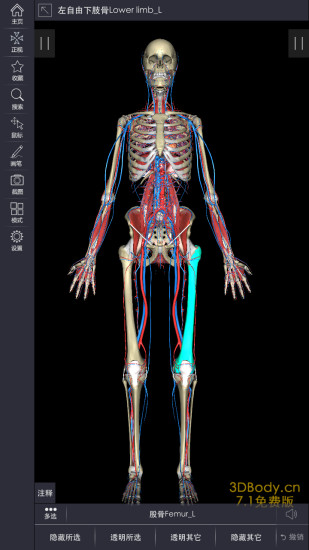

3dbody系统解剖手机版是专为医学行业打造的掌上人体解剖学习软件,详细的三维解刨图片,解释详尽。3DBody系统解剖手机版是系统模块,相较于局部模块版,解剖更加的详细,需要的赶紧下载吧。

3Dbody系统解剖提供了男体一套全三维的数字模型,2000多个人体结构,涵盖了人体所有解剖系统。

3DBody作为集大成者,不仅数据详实,而且操作功能强大,国内外高度领先,通过本软件实时三维操作,轻易获得层层解剖人体的机会。作为内容最全面的3D解剖app,电脑版本已经被证实为最受欢迎的医学软件之一。

软件包括人体十二大系统的3D解剖.经络穴位和反射区,同时提供大量肌骨康复动画,全部三维体验,界面精美,内容专业,操作体验佳。